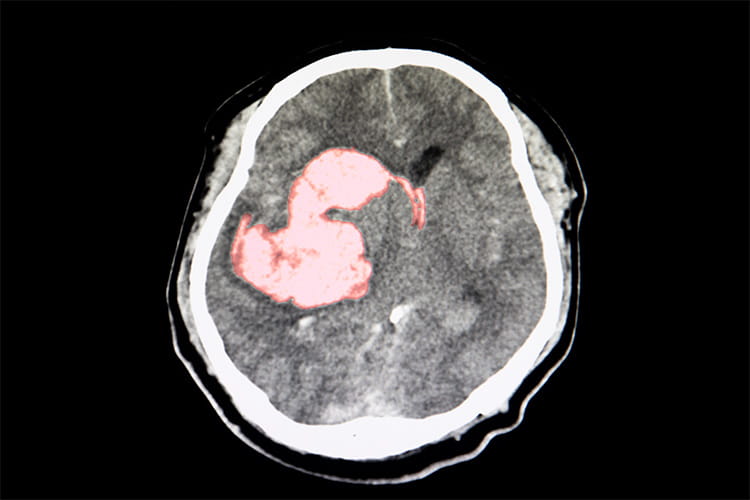

- Approximately 10% of the 795,000 strokes per year in the United States are intracerebral hemorrhages (ICHs).

- ICHs are the deadliest form of acute stroke with early mortality ranging between 30%-40%.

- The 2022 version of the Guideline for the management of patients with Spontaneous Intracerebral Hemorrhage focuses on primary and secondary prevention, acute inpatient care and post stroke rehabilitation.